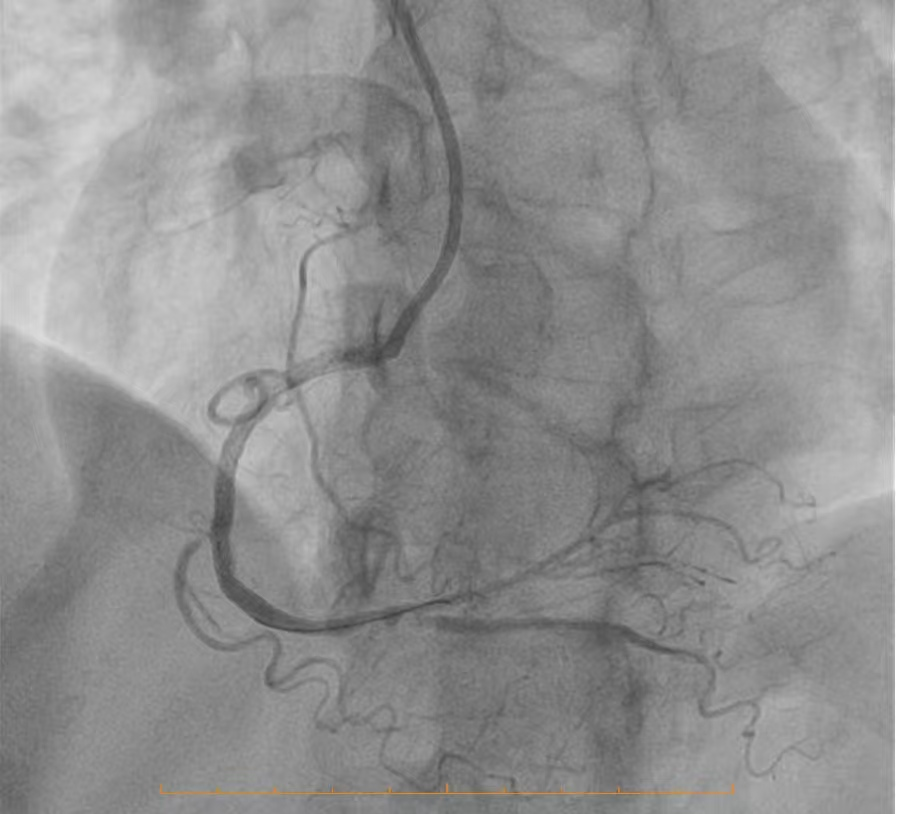

开通后的冠脉影像4

面对如此复杂的病情,李晓君主任与卢永艳主任带领团队进行了周密的术前讨论。她们权衡利弊,最终决定迎难而上,为患者实施冠脉介入开通治疗。这一决策,源于对自身技术的充分自信,更源于为患者寻求最佳治疗效果的仁心。手术当日,导管室内气氛紧张而有序。在李晓君主任和卢永艳主任的精准操作下,导管导丝如同被赋予了生命,在纤细的血管中游刃有余地前行。他们沉着冷静,目光如炬,每一个动作都精准有序,力求在解除病痛的同时,最大限度减少对患者的生理干扰。挑战最大的无疑是开通右冠脉那段已经完全闭塞的血管。这需要术者凭借高超的手法,在几乎无路可循的病变中,重新开辟出一条生命的通道。团队密切配合,运用娴熟的技术,巧妙应对各种突发情况。最终,奇迹诞生——原本闭塞的右冠脉被成功开通,并顺利植入了支架,恢复了畅通的血流。整个高难度手术过程,仅用时约半小时顺利结束!这不仅是一次技术上的胜利,更是一次对患者身心的最大保护。手术避免了开胸的巨大创伤,仅通过一个小小的穿刺点,便解除了困扰患者多时的顽疾,为他赢得了更高的生活质量和宝贵的生命希望。